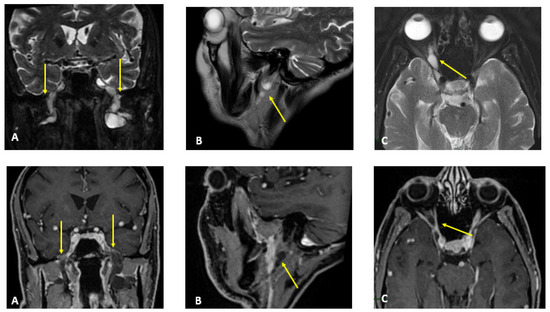

Figure 1.

MR T2-weighted (top) and T1-weighted fat post-contrast contrast images (bottom). The images in (A) are in the coronal plane, those in (B) are in the sagittal plane and those in (C) are in the axial plane. The images show thickened and pathological cranial nerves with a cystic appearance, high signals in T2w images and almost no contrast enhancement. In both (A), yellow arrows indicate pathological V3 branches of the trigeminal nerve (transverse diameter after the foramen ovale: left 3.8 mm; right 10 mm); in both (B), yellow arrows indicate pathological facial nerve in the intraparotid course (transverse diameter in intraparotid course: left 6.7 mm vs. right 2.2 mm); in both (C), yellow arrows indicate pathological right V1 branch of the trigeminal nerve (transverse diameter after superior orbital foramen: right 6.9 mm vs. left 2.3 mm).

Figure 2.

MR (multiplanar reconstructions) of 3D cube neurography images show pathological, thickened cranial nerves along their extracranial course, with some cystic-like components. The images show the involvement of trigeminal branches V1 in ((D)—yellow star), V2 in ((B,D)—curved arrows with a transverse diameter after inferior orbital foramen: left 1.8 mm; right 2.6 mm) and V3 from its passage in the foramen ovale (asterisks in (A,B)) to its lingual (arrowheads in (B,D)) and alveolar divisions (thick arrows in (B–D)); the involvement of the left facial nerve in its intraparotid course (thin arrows in (A,C)) and the hypoglossal nerve (open arrow in (B), transverse diameter at C1 level: left 4.6 mm; right 2.1 mm).

MR findings: brain and spinal MR were negative for pathological contrast enhancement of the roots of the cauda equina and radicles emerging from the spinal cord. Instead, swellings along the extracranial course of some V and VI cranial nerve branches had been reported (Figure 1). It was decided to integrate the study with MR neurography of the cranial nerves and the lumbosacral and brachial plexuses, which showed diffuse hypertrophy of the cranial nerves, and in particular of the oculomotor, trigeminal, facial, and hypoglossal (Figure 2) nerves with bilateral associations and asymmetric hypertrophy of the lumbosacral (Figure 3 and Figure 4) and brachialis (Figure 3 and Figure 5) plexuses.